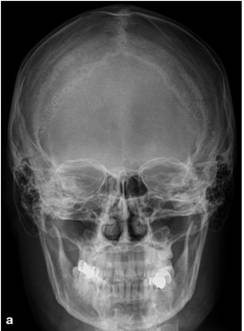

На рентгенограммах глазницы в носоподбородочной,

носолобной и боковой проекциях визуализируются вход в глазницу, ее стенки,

иногда малое и большое крылья клиновидной кости, верхняя глазничная щель (см.

рис. 1).

Рис. 1. Рентгенограммы глазниц в носолобной (а),

носоподбородочной (б) и боковой (в) проекциях